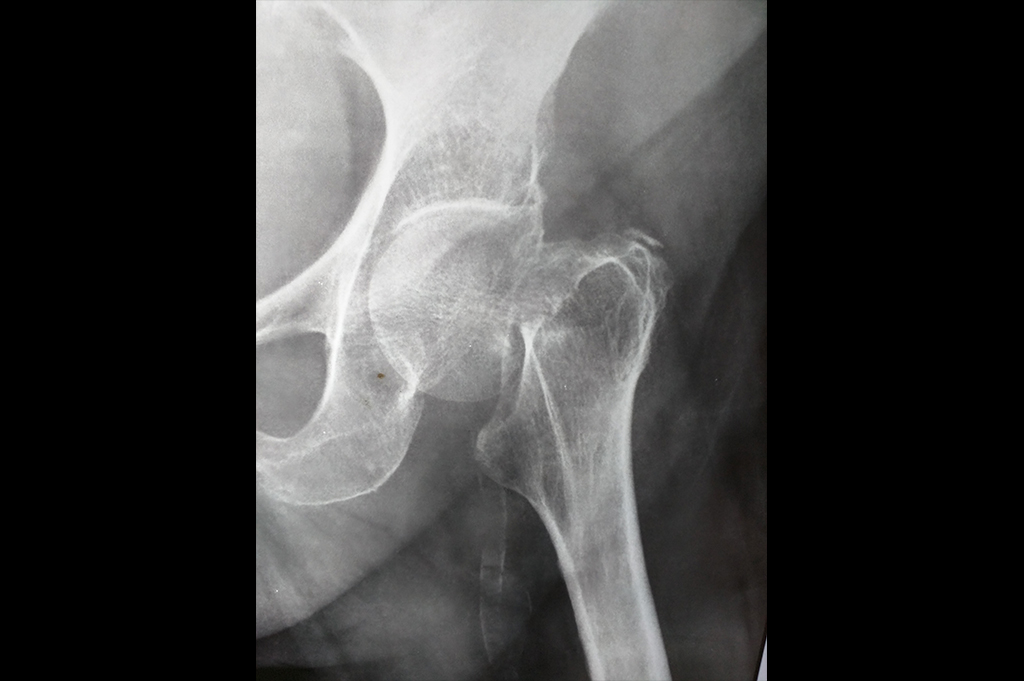

Neck Femur Fracture